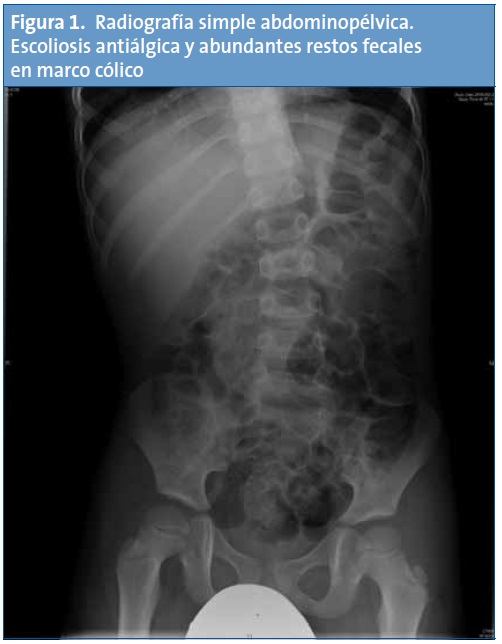

La ecografía de la cadera y la radiografía abdominopélvica fueron normales, a excepción de la posición antiálgica en esta última (Fig. 1).